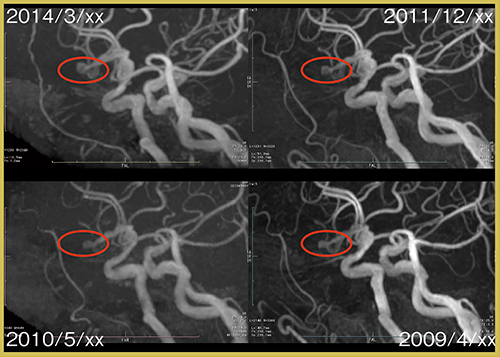

動脈瘤では,経時的な増大などをきちんと評価することが重要であるため,MRA画像(図5)や元画像を過去画像と比較することが大切であり,三次元レジストレーションは非常に有用である。また,2D画像でも位置合わせを試みたところ,脳腫瘍などの大きな病変であれば比較読影が可能であった。

図5 MRA画像のレジストレーション(脳動脈瘤)